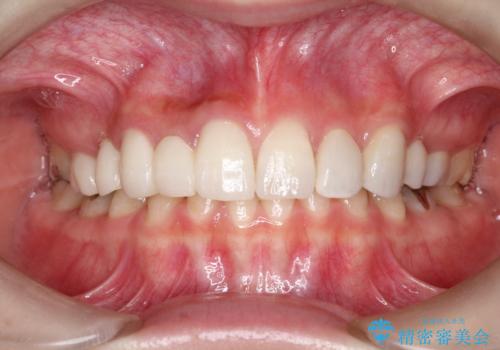

かぶせものと歯ぐきの境目が黒い 40代女性

保険のかぶせ物・詰め物を金属を使わないセラミックへ 自然な見た目へ